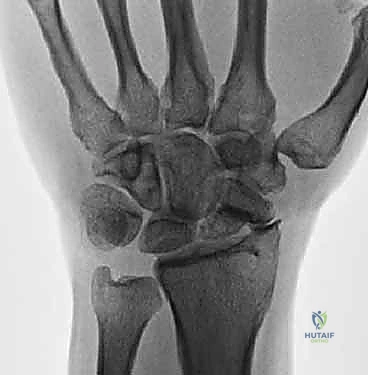

لفهم طبيعة متلازمة SNAC والعملية الجراحية، يجب علينا أولاً الغوص في التركيب التشريحي المذهل لمفصل الرسغ. يتكون الرسغ البشري من ثماني عظام صغيرة تُعرف بعظام الرسغ (Carpal bones)، مرتبة في صفين (صف قريب وصف بعيد).

العظم الزورقي (Scaphoid Bone) هو العظم الأهم والأكثر تعقيداً في هذه المجموعة. يعمل هذا العظم كجسر رابط ومحور ارتكاز بين الصفين القريب والبعيد لعظام الرسغ. هذا الموقع الاستراتيجي يجعله عرضة لضغط ميكانيكي هائل أثناء حركات اليد اليومية، ولكنه في الوقت نفسه يجعله الأكثر عرضة للكسور.

المشكلة الكبرى التي تواجه العظم الزورقي تكمن في التروية الدموية (Blood Supply). الدم يدخل إلى العظم الزورقي من الجزء البعيد (Distal pole) ويتجه نحو الجزء القريب (Proximal pole) في اتجاه عكسي (Retrograde). لذلك، عند حدوث كسر في منتصف العظم، ينقطع الدم عن الجزء القريب، مما يؤدي إلى عدم التئام الكسر (Nonunion) وفي كثير من الأحيان موت العظم (Avascular Necrosis).

متلازمة SNAC (Scaphoid Nonunion Advanced Collapse) هي حالة تدهور تدريجي ومأساوي لمفصل الرسغ. تبدأ القصة بكسر في العظم الزورقي (غالباً بسبب السقوط على يد ممدودة). إذا لم يتم تشخيص هذا الكسر أو لم يلتئم بشكل صحيح، فإن العظم الزورقي ينقسم إلى قطعتين تتحركان بشكل غير طبيعي ومستقل عن بعضهما البعض.

هذه الحركة غير الطبيعية تخلق احتكاكاً مستمراً (Micro-trauma) مع العظام المجاورة، وتحديداً عظم الكعبرة (Radius). بمرور الوقت (أشهر أو سنوات)، يؤدي هذا الاحتكاك إلى تآكل الغضاريف الناعمة التي تغطي العظام، مما يسبب خشونة مفصلية شديدة (Osteoarthritis).